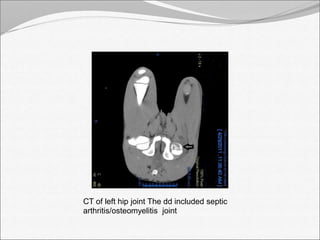

CT of left hip joint The dd included septic

arthritis/osteomyelitis joint

CT of lefthip joint The dd included septic arthritis/osteomyelitis joint